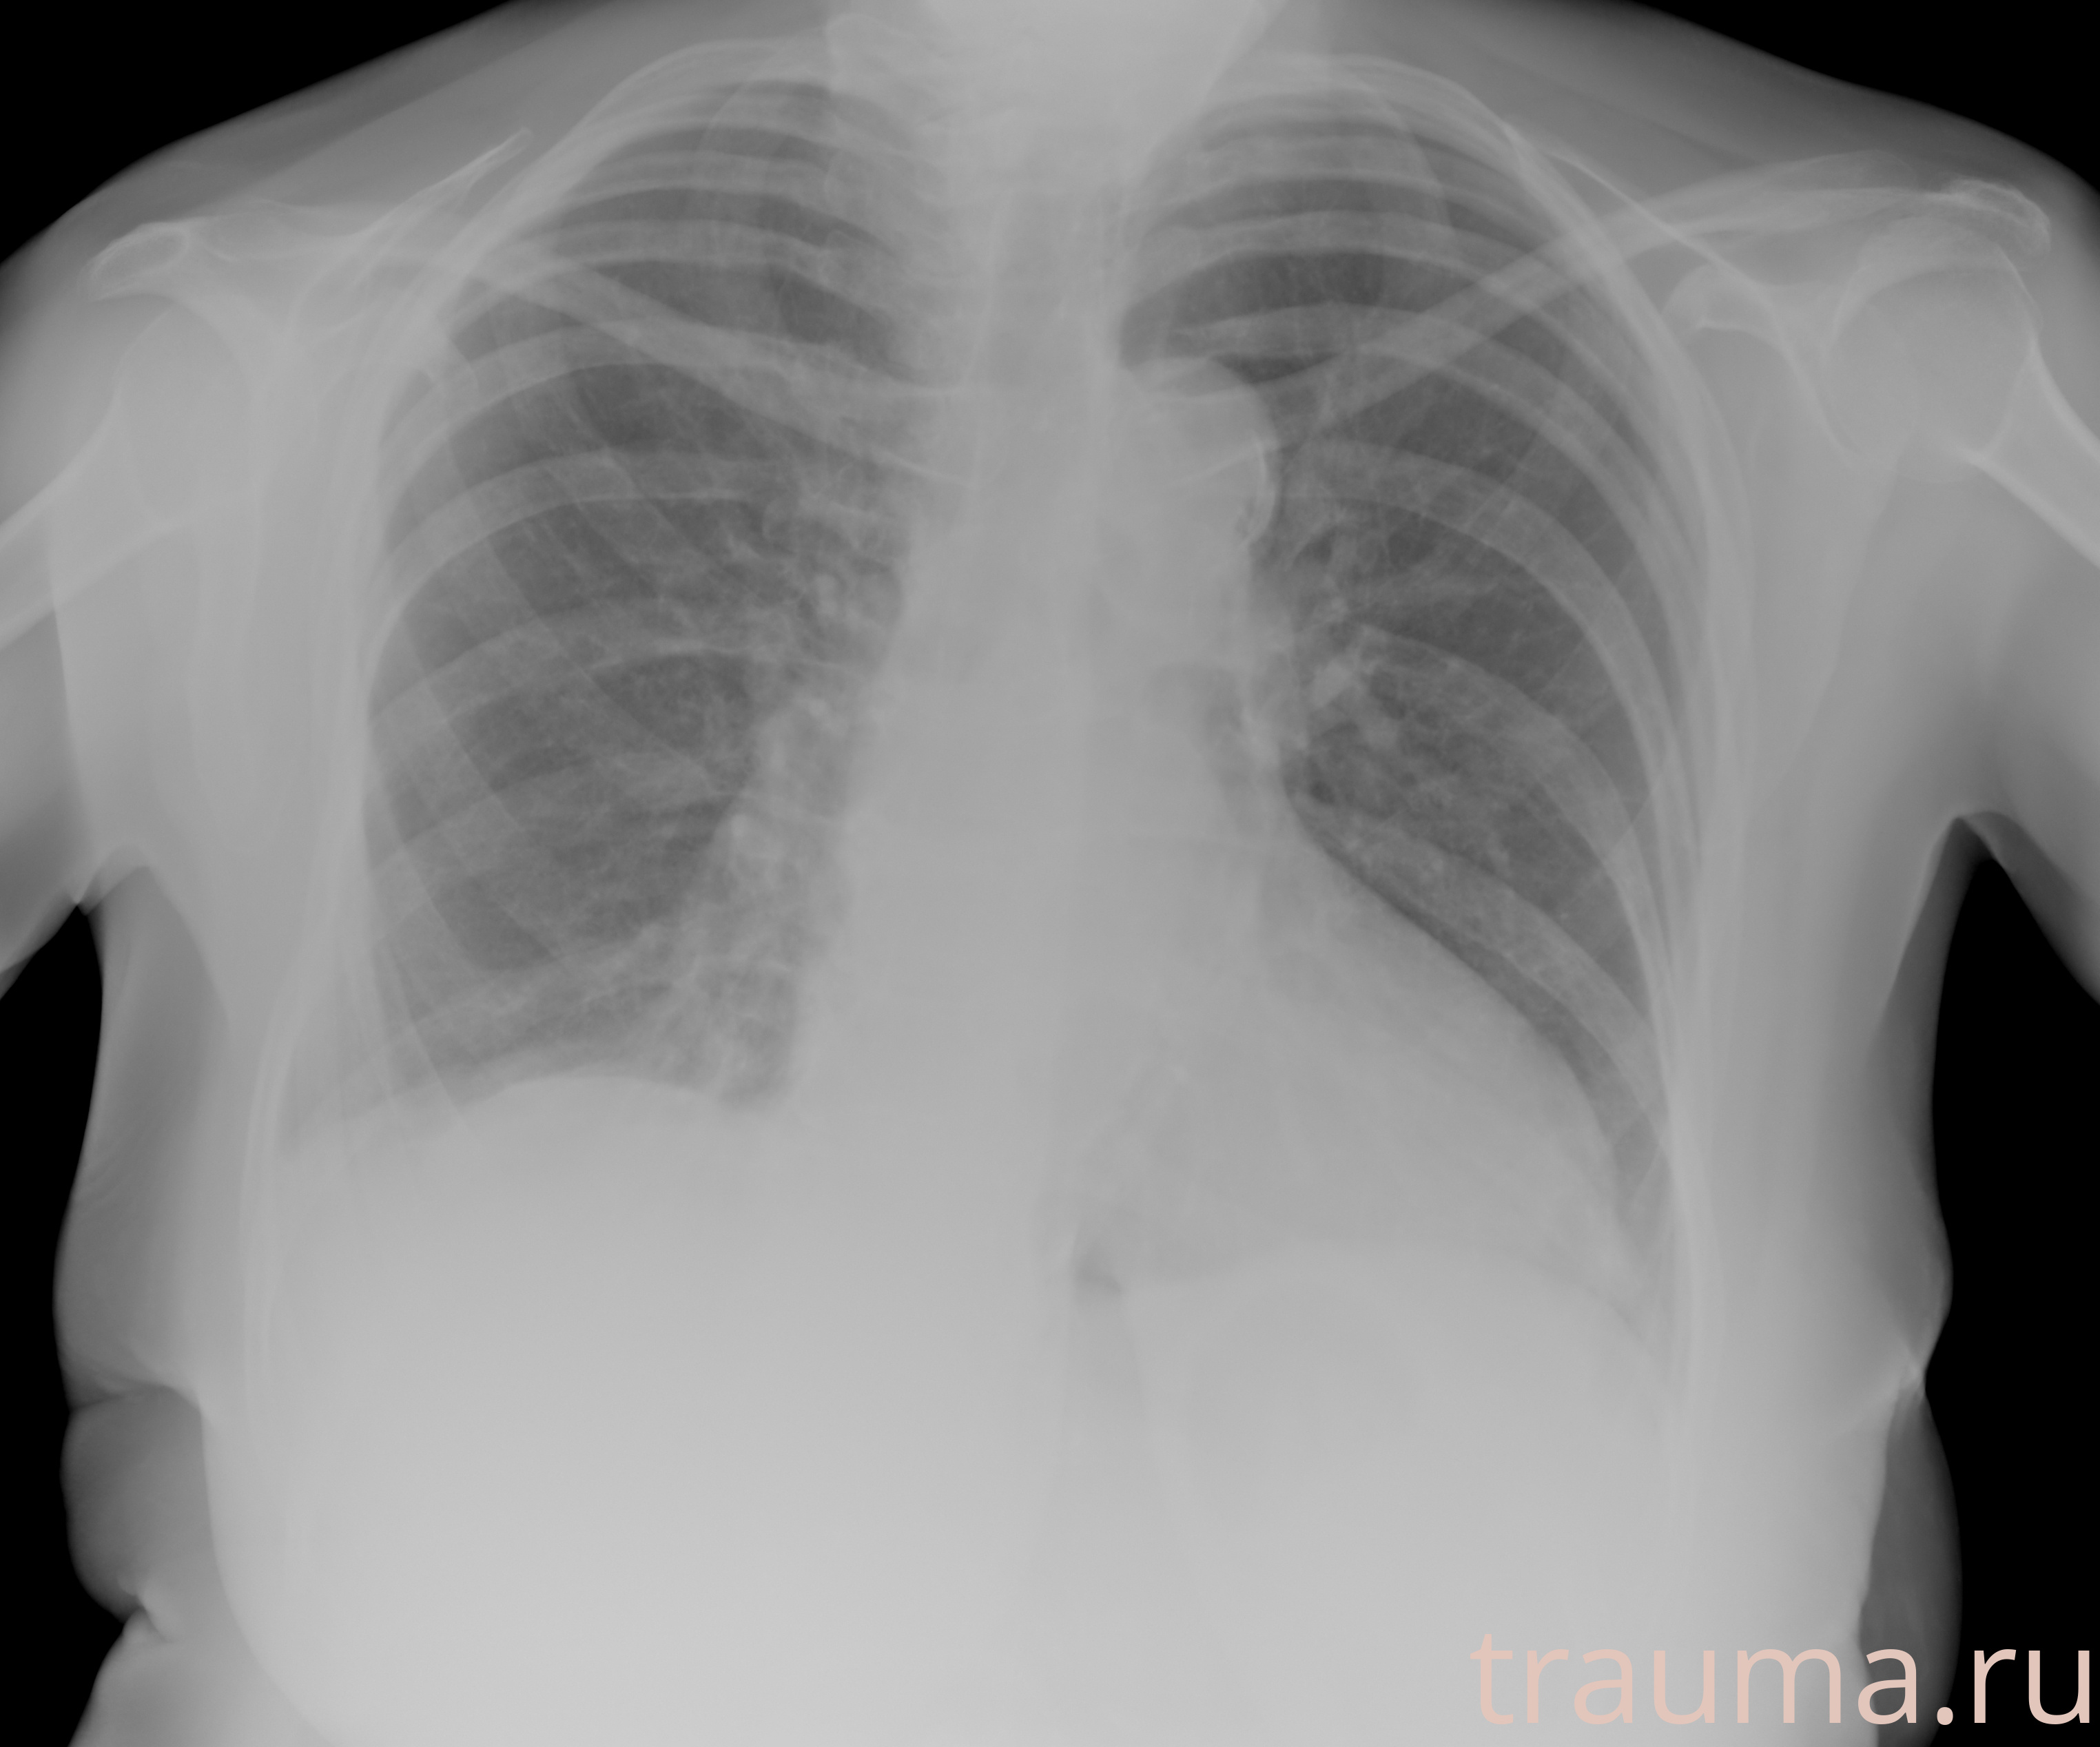

Рентген на дому: по вашему адресу приезжает врач-рентгенолог, травматолог-ортопед с мобильным рентгеновским аппаратом, проводит диагностику травмы или заболевания, делает необходимые рентгенограммы, дает рекомендации по дальнейшему лечению. Получить качественные снимки в домашних условиях возможно благодаря уникальной методике, разработанной МосРентген Центром для института  Склифосовского